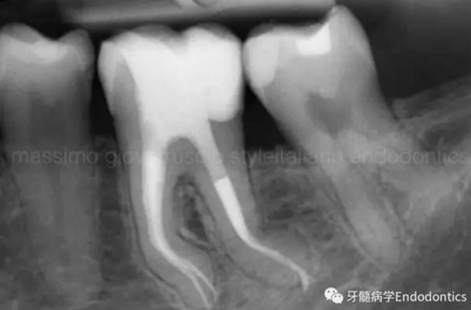

圖6.術后X線片顯示在根管機械預備后保留了原始的根管解剖形態(tài)結構。冠方預敞和探查保證了對整個根管解剖形態(tài)結構的保護。

圖11.術后X片顯示完成了根管的三維充填并很好地保留了復雜的解剖形態(tài)結構。